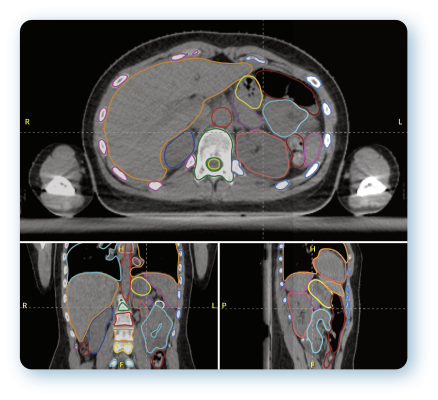

The partnership will commence with AutoContour, Radformation’s AI-driven contouring solution featuring 200 structure models, a robust toolset and image registration to accelerate the pre-treatment planning process, and RadMachine, a cloud-based platform used to streamline Machine QA to ensure the safety and optimal performance of treatment delivery systems, imaging technology, and ancillary equipment. This collaboration aims not only to enhance workflow efficiency and increase treatment accuracy but most importantly, to significantly improve patient outcomes.